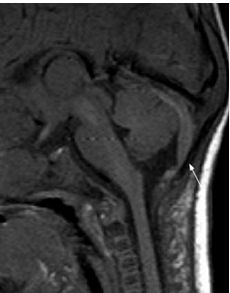

DISRAFISMO ESPINAL OCULTO